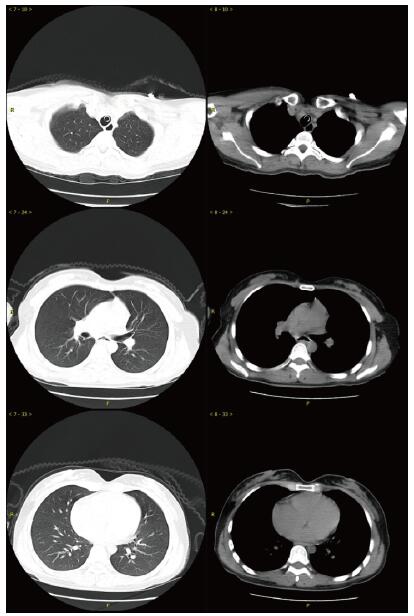

当晚20时到达本院,入院时患者昏迷,血压低、心肌损伤、轻度心衰, 低氧血症, 肝损伤。相关实验室检查:血气PaO2 44 mmHg,生化指标谷丙转氨酶(ALT)528.8 U/L,谷草转氨酶(AST)780.9 U/L,胆红素正常,尿素氮(BUN)3.6 mmol/L,肌酐(Cr)125.7 μmol/L,血糖7.88 mmol/L,心肌肌酐蛋白(cTnT)55.94 ng/mL,N末端B型利钠肽原(NT-pro BNP)495.7 pg/mL,神经元特异性烯醇化酶(NSE)47.46 ng/mL。胸部CT未见明显异常(图 1),头颅CT未见明显异常(图 2A)。给予异甘草酸镁保肝,乙酰半胱氨酸抗氧化,兰索拉唑保护胃黏膜,并予血液灌流治疗一次。

| 图 1 患者入抢救室时肺部CT影像 |

次日晚间收住入院。住院第2天监测血压99/72 mmHg。实验室检查:cTnT 245.4 ng/L,NT-pro BNP 18.57 pg/mL,BUN 2.68 mmol/L,Cr 40.5 μmol/L,血钾3.82 mmol/L。血气:PO2 116 mmHg,pH 7.498, Lac 1.58 mmol/L。并CRRT治疗:治疗前APTT为32.2 s,阿加曲班抗凝,治疗剂量40 mL/(kg·h)。第3天继续CRRT治疗,阿加曲班抗凝,监测APTT为62.9 s(为正常值2倍)。第4天停CRRT, 记录自发尿量1 920 mL /24 h。第5天神志逐步转清,有指令动作,自主呼吸良好,停机械通气。脱机拔管后查颅脑CT双侧基底节区及脑干低密度影, 考虑中毒性脑病改变(图 2B),胸部CT未见明显异常。监测APTT为26.7 s。第7天患者再次昏迷,并有呼吸急促,脉氧下降。再次行气管插管呼吸机支持。监测肝功能进一步好转(ALT 187.7 U/L,AST 92.2 U/L)。第8天17时发现患者瞳孔不等大,左侧3.5 mm,右侧4.5 mm, 对光反射消失,即查颅脑CT示右侧基底节区出血(图 2C)。家属要求保守治疗。第9天患者处于深昏迷状态,家属放弃继续治疗出院。出院一周后随访患者死亡。

哒螨灵口服中毒后机体细胞内呼吸功能抑制,导致细胞缺氧,无糖酵解,乳酸快速堆积,机体迅速出现代谢性酸中毒,重要脏器灌注不足,早期即可表现肝功能异常甚至肝衰竭;心肌酶谱增高,心肌收缩力减低,胰腺功能受损,血淀粉酶增高,血糖应激性增高[3]。由于人体脑组织供应的血流非常丰富,因此对缺氧表现也非常敏感。但哒螨灵中毒并发脑病报道较少,并发脑出血者罕见。该例患者中毒后出现恶心呕吐,提示该药对胃肠道有刺激性;后出现多系统损伤。早期即出现意识障碍,并渐加重至昏迷,有脑神经元损伤,但早期头颅CT未见明显异常;患者有严重低血压,需要大剂量血管活性药物维持血压;患者严重低氧血症,需要呼吸机支持,但肺部影像学未见明显异常;患者有乳酸酸中毒、肝肾功能损伤和心肌受损,但上述损伤大多在支持治疗2~4 d后完全正常或出现明显好转。但第5天头颅CT提示患者出现中毒性脑病表现,患者神志在短暂好转后又再次恶化,第8天原右侧基底节区水肿部位出现脑出血。